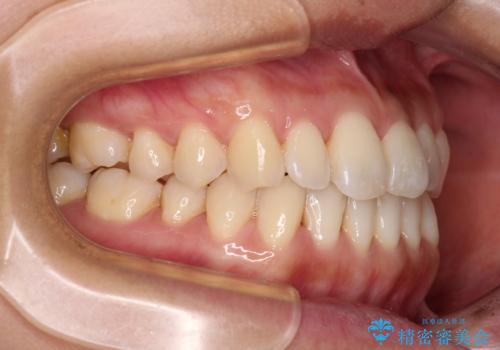

- 前歯のデコボコで前方に出ていることを気にして来院された患者様です。

上顎前歯が捻れて前方に飛び出しており、下顎前歯もそれに沿うようにデコボコとなっていました。

IPR(歯と歯の間を削る処置)によりスペースを獲得して上下顎前歯のデコボコを改善し、飛び出している前歯が引っ込むように設定し、インビザラインにて矯正治療を行うこととしました。

装着時間を守ってくださったので、予定通りの期間で終えることができました。インビザライン特有の、奥歯の咬み合わせの問題もなく、しっかりと歯列を改善することができました。